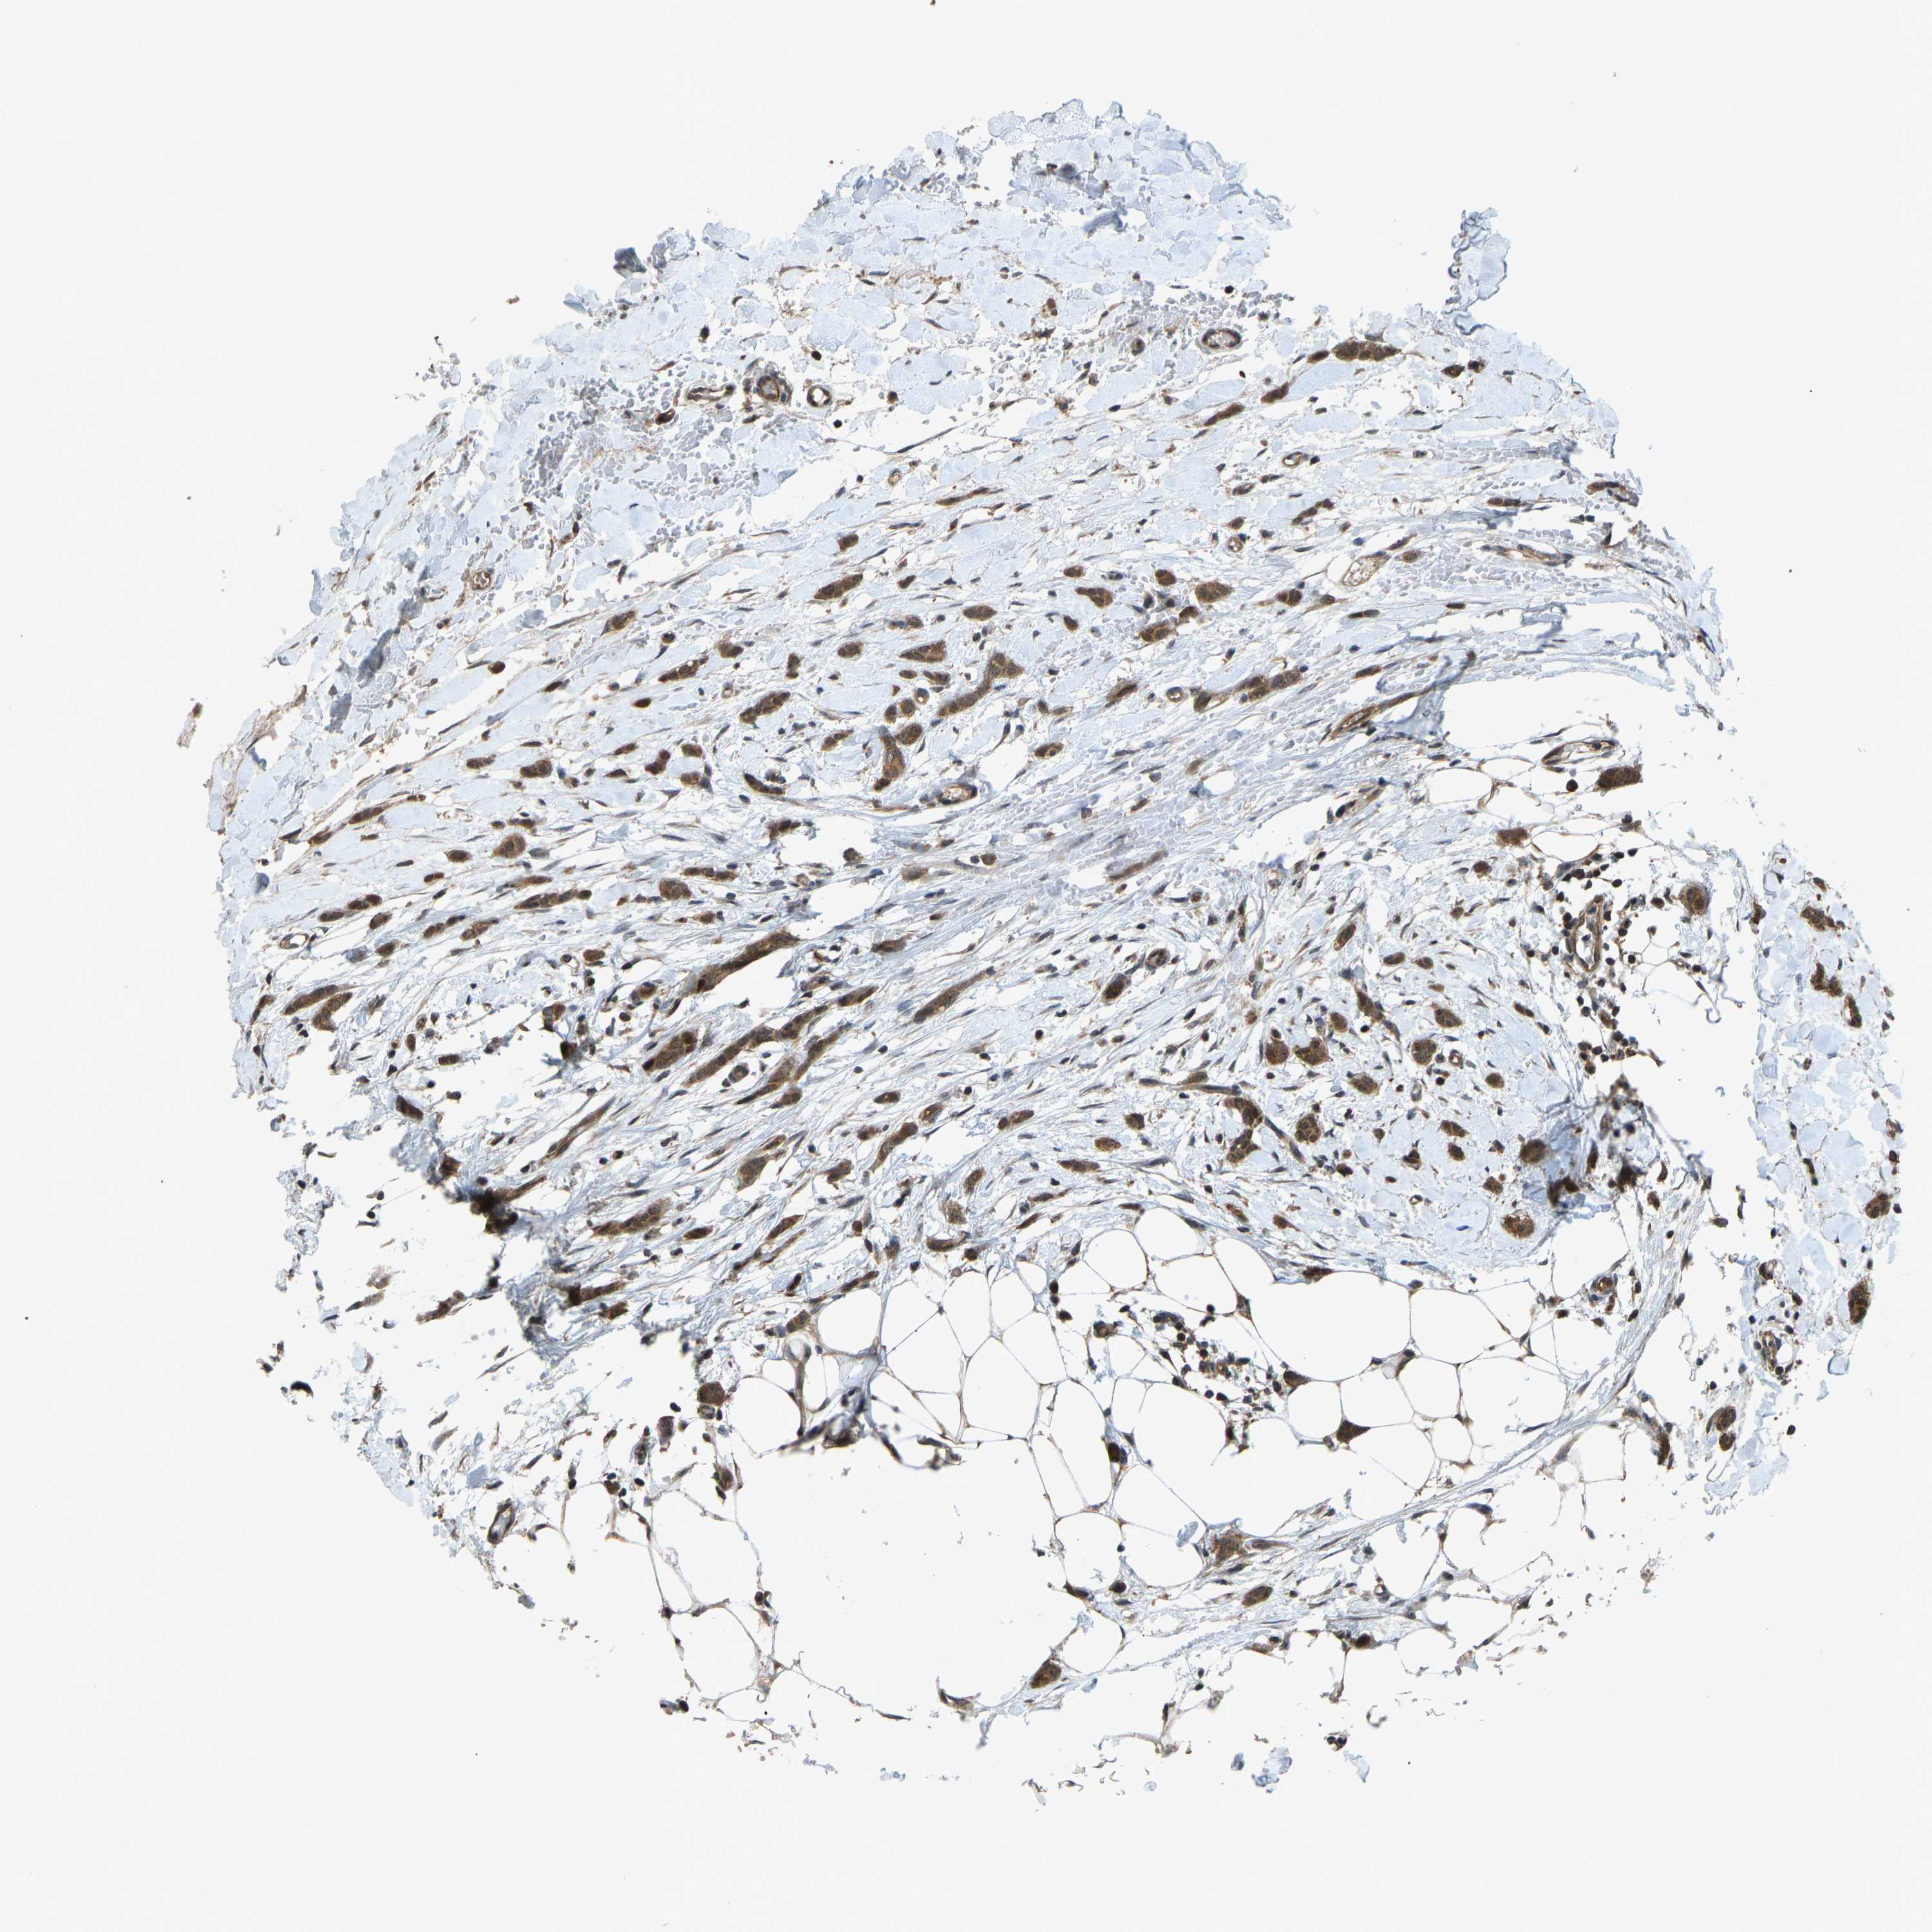

BRCA TCGA BRCA VALIDATION PROTEIN EXPRESSION